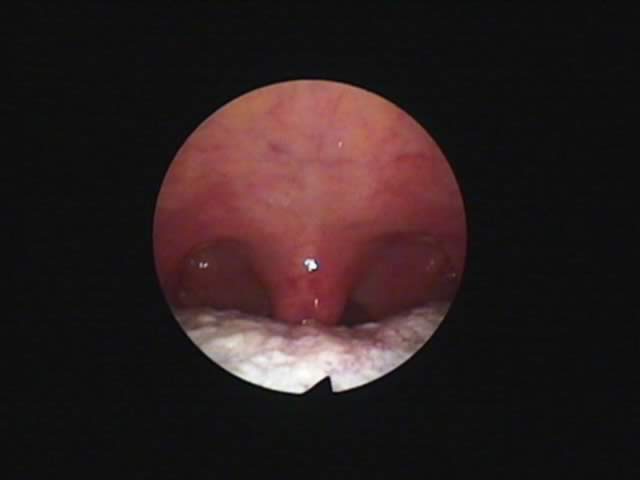

1) 手術前、口蓋垂(のどちんこ)が太く長く舌にくっついており、その横の粘膜も幅が広い。いびき改善手術をすることとなりました。 2) 外来(日帰り手術)手術後50日、70%のいびき音が改善したと本人がいっております。のどがひろくなりました。